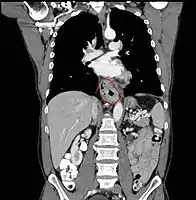

- Lower thoracic esophagus and EG junction:

- Inferior pulmonary veins to the stomach; includes the intraabdominal portion of the esophagus

- By endoscopy, 30 to 40 cm

- Resectability often limited:

- Lack of fibrous serosa to prevent local spread

- Rich lymphatic network in submucosa and muscularis that allows longitudinal and circumferential drainage